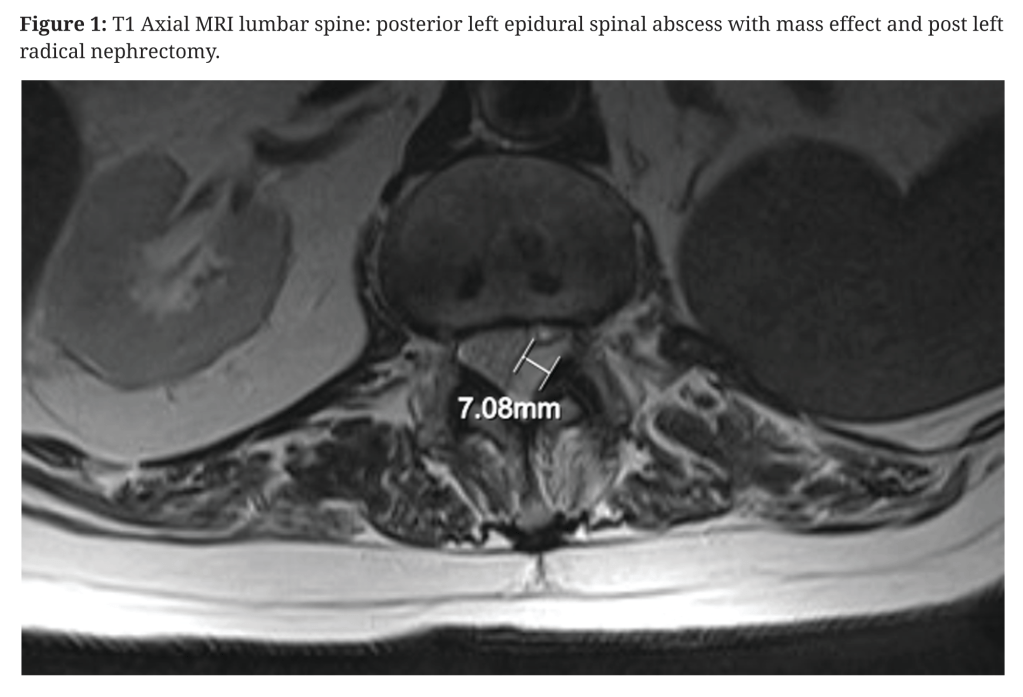

So, let’s have a look at this recent case.[1] An 89-year-old man with type 2 diabetes and diabetic nephropathy presented with a 2-week history of poorly characterised left flank and hip pain. He had undergone a left nephrectomy at some point in the past (not detailed) and attributed his pain to a fall some 3 months previously. He sought acupuncture for pain relief, but the timing is not reported. He was afebrile with raised CRP (122) and WCC (18.57). On day four of admission, he developed retention of urine and a subsequent MRI demonstrated a posterior left epidural abscess extending from T11 to L4/5.

The discussion starts with: “Inoculation of the infection-prone fat in the epidural space…”, and goes on to quote Darouiche’s estimates from NEJM that I mentioned at the start – about half of cases are via haematogenous spread and a third contiguous spread.[4] Inoculation implies the authors have assumed an acupuncture needle pushed Staph aureus from the skin into the epidural space, but this is very unlikely with a filifiorm needle since there is no bore to carry the bugs in, and most would be wiped off in superficial layers. In addition to this I doubt many acupuncture practitioners in New Zealand insert needles as far as the epidural space on a routine basis. In this case, based on the axial MR image in Figure 1 it would require a 50mm needle insertion close to the midline.